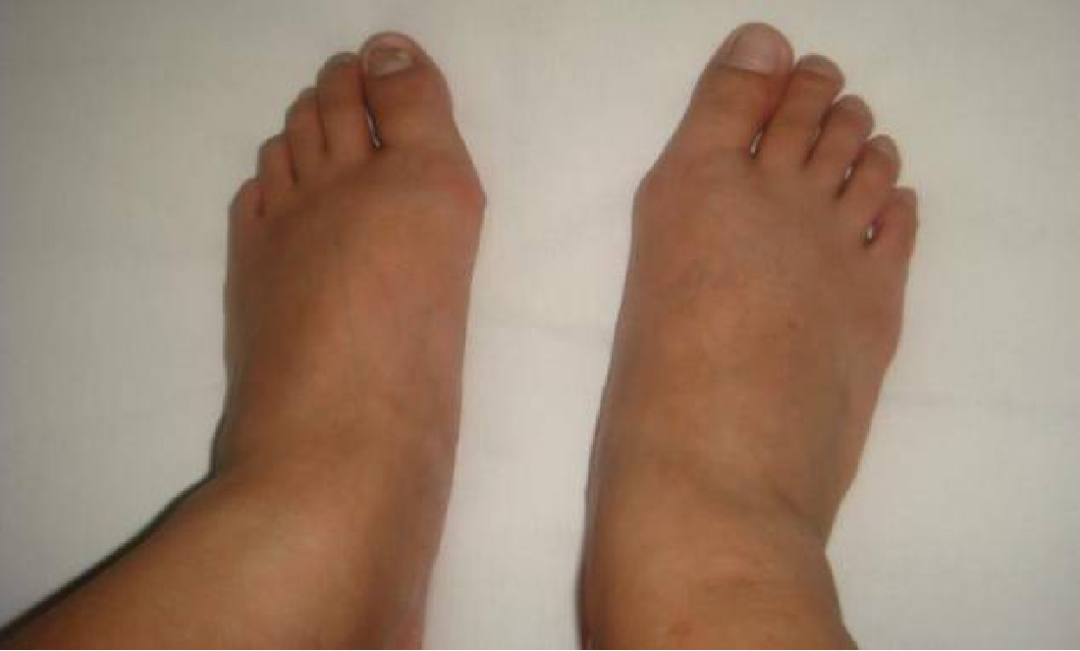

拇外翻也叫大脚骨病,是指拇趾向外偏斜超过正常生理角度的一种足部畸形,是目前最常见的足病之一。一般认为拇趾的外翻角>15º可诊断为拇外翻。

拇趾外翻后,第一跖骨头内侧骨赘形成,与鞋面摩擦,形成滑囊炎,成为拇囊炎在第一跖骨头背侧突出并伴有滑囊炎者,又被称为背侧拇囊炎

由于拇外翻后常常伴有足的其他部位病变,如锤状趾、跖骨痛、小趾滑囊炎、扁平足等,因此,又有人称拇外翻为“拇外翻复合体”或“拇外翻综合征”

查体一般检查:一般检查要观察足部皮肤的状态,足部的血运情况,感觉,肌肉的状态,步态。

局部检查:局部检查要在足非负重和负重状态下分别完成。

非负重位的检查

• 第1跖趾关节内侧或背内侧肿物突出,表面皮肤可有胼胝

• 局部皮肤红肿可形成拇囊炎

• 拇囊部位的压痛